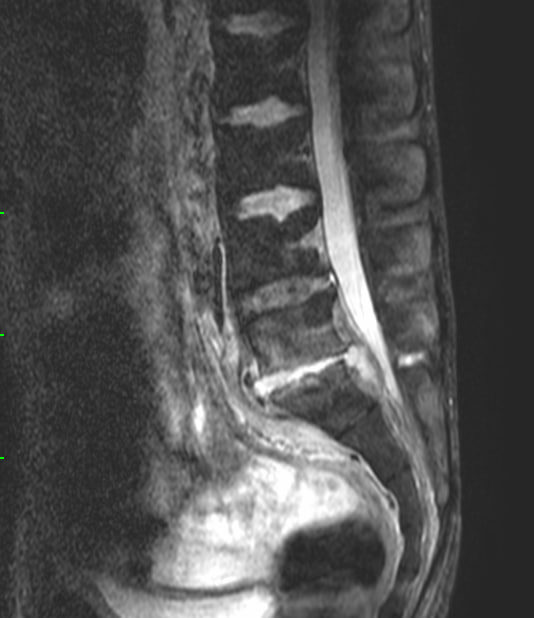

По опыту скажу: когда видишь вот такого, худющего пациента, с таким черным (особенно на Т1, хотя и на Т2, как правило, тоже) костным мозгом, да ещё и со спондилодисцитом, можно не сомневаться, что перед тобой - ВИЧ-инфицированный, и CD4-клеток у него уж точно меньше 150.